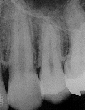

2年後の右上6二年後